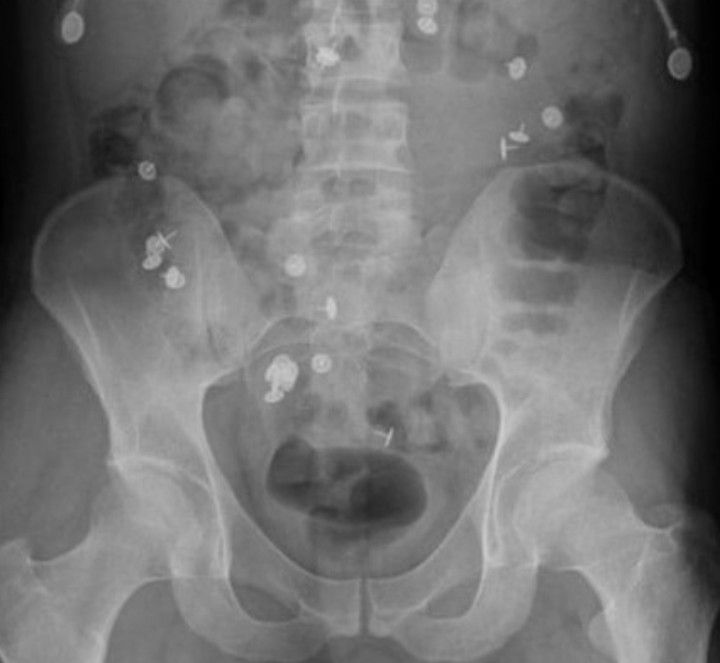

A Suicide Attempt

Thumb pins ingested in a suicide attempt.